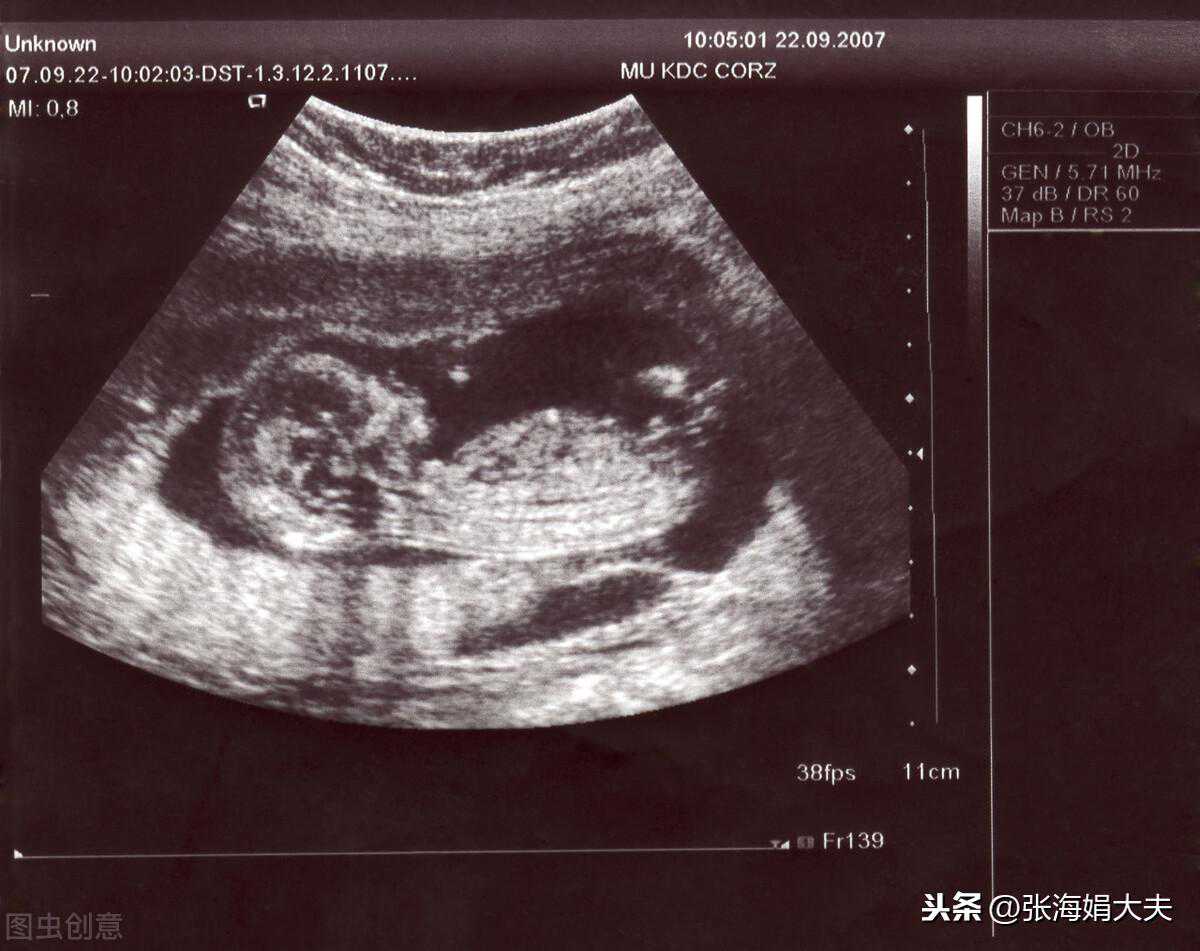

现在怀孕已经有三个月的时间了,孕检良好宝宝发育一切正常,恭喜她们如愿的拥有了自己的宝宝,开心开心!希望大家也都能如此好孕~